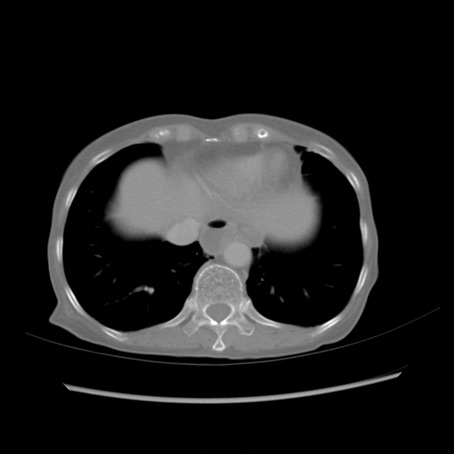

症例25(横断像)

【症例】80歳代女性

【主訴】胸のつかえ感

【現病歴】約9時間前に食後から胸のつかえた感じあり、嘔吐あり、来院。

【既往歴】胃癌(全摘)、胆摘、虫垂炎

【身体所見】心窩部に圧痛あり、反跳痛なし。

【データ】WBC 5700、CRP 0.05